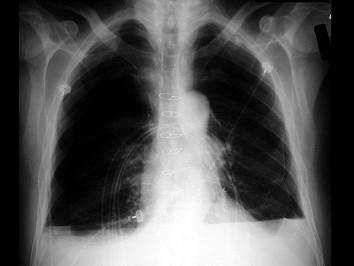

下列哪张图片是脓胸X线表现 ( )A、B、C、D、

问题 下列哪张图片是脓胸X线表现 ( )

选项 A、 B、 C、 D、

答案 B